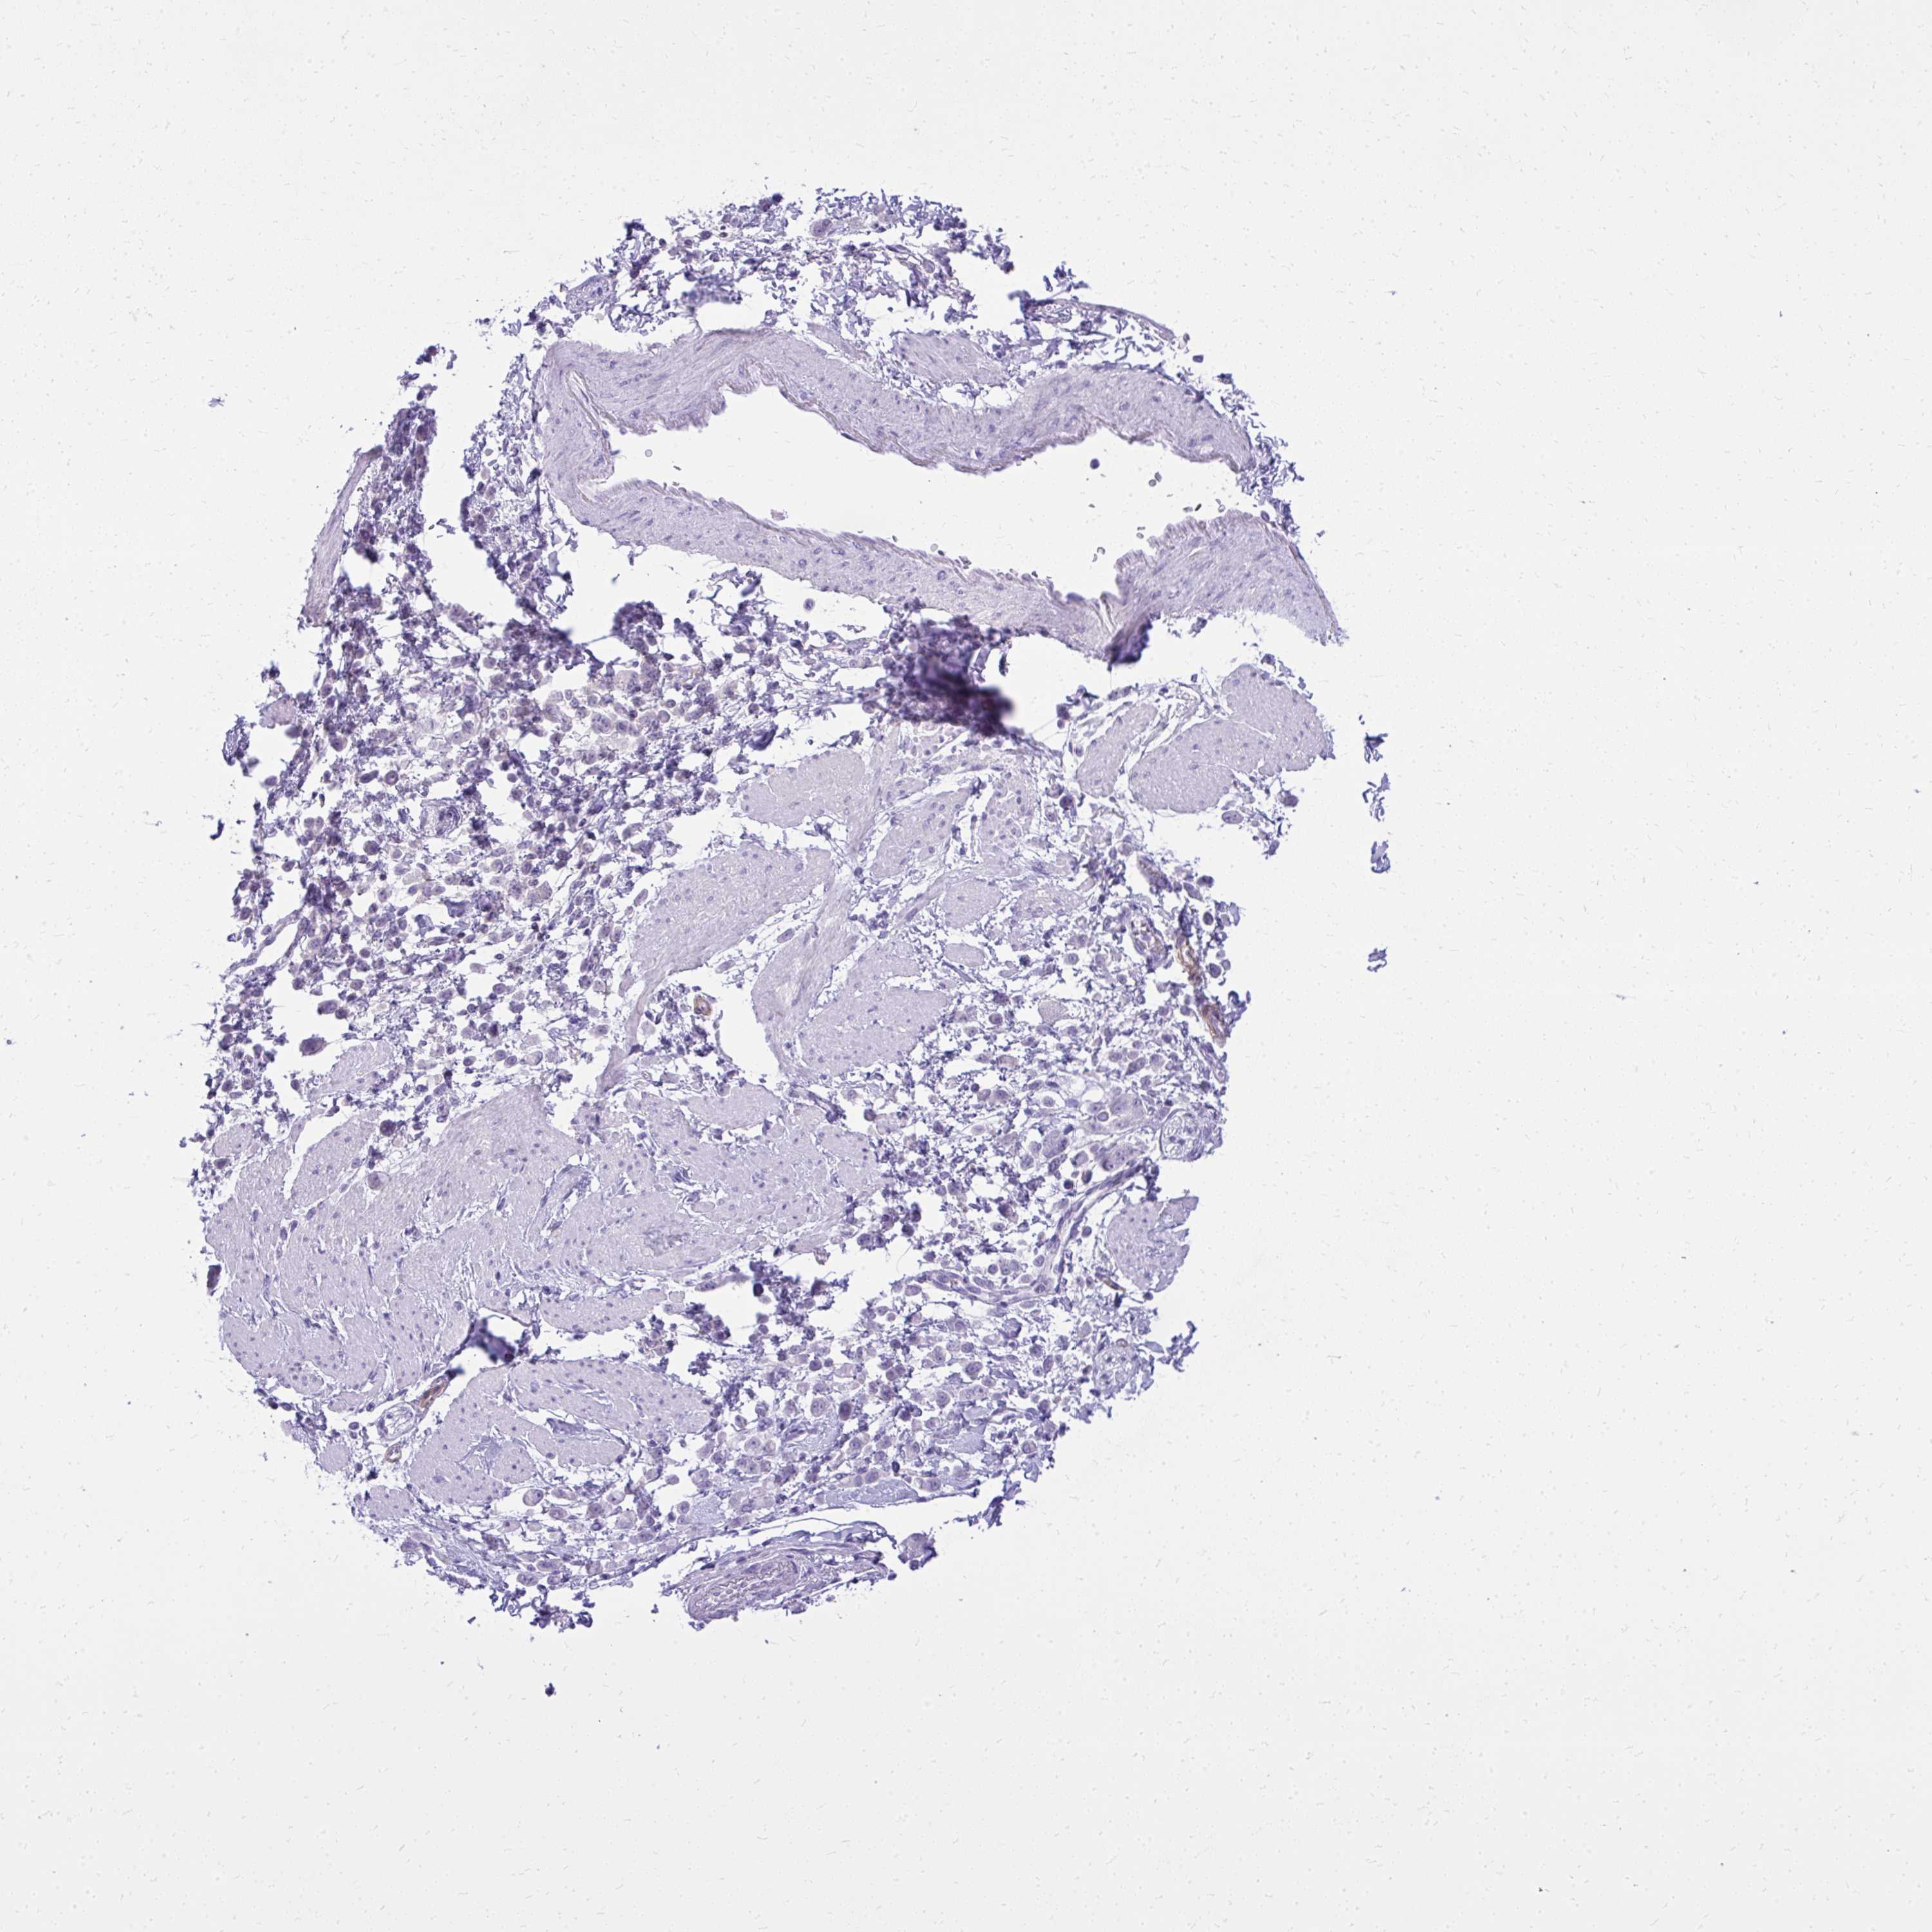

PANCREATIC CANCER - Protein expressioni

A mouse-over function shows sample information and annotation data. Click on an image to view it in a full screen mode. Samples can be filtered based on level of antibody staining by selecting one or several of the following categories: high, medium, low and not detected. The assay and annotation is described here.

Note that samples used for immunohistochemistry by the Human Protein Atlas do not correspond to samples in the TCGA dataset.

Antibody stainingi

Antibody staining in the annotated cell types in the current human tissue is reported as not detected, low, medium, or high, based on conventional immunohistochemistry profiling in selected tissues. This score is based on the combination of the staining intensity and fraction of stained cells.

Each image is clickable and will lead to virtual microscopy that enables deeper exploration of all samples and also displays staining intensity scores, fraction scores and subcellular localization as well as patient and tissue information for each sample.

Antibody HPA057666

Antibody HPA059092

Adenocarcinoma, NOS